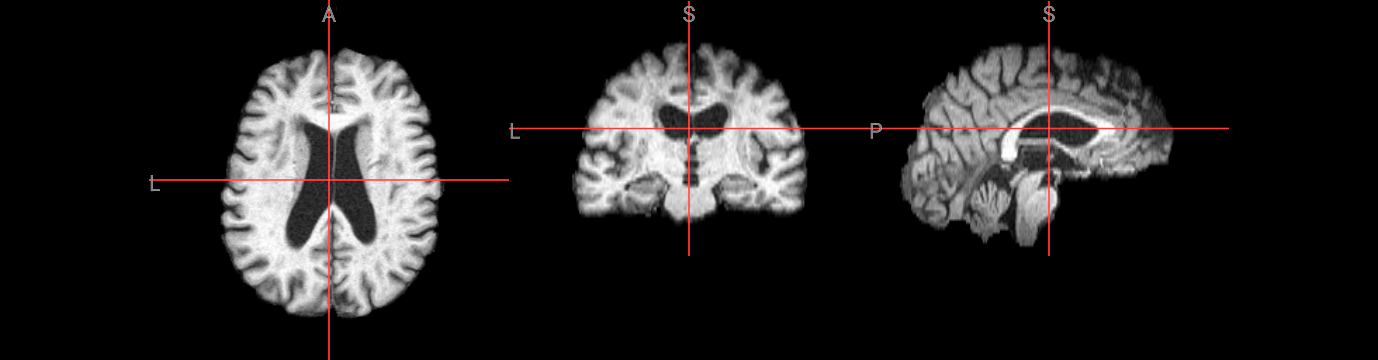

Varying the fractional intensity threshold parameter (-f)#

The fractional intensity threshold is BET’s key parameter for distinguishing brain tissue from non-brain tissue. This interactive demonstration shows how different -f values affect brain extraction results:

Lower values (e.g., -f 0.2): More inclusive extraction - captures more tissue but may include non-brain areas

Higher values (e.g., -f 0.8): More conservative extraction - tighter brain boundary but may exclude brain tissue

Default (-f 0.5): Balanced approach suitable for most cases

The folowing visualization shows three different threshold results overlaid on the original image, demonstrating how this single parameter dramatically changes the extraction outcome.

nv.load_volumes( [{"path": "./output/structural_brain_f02.nii.gz", "colormap": "gray"},

{"path": "./output/structural_brain.nii.gz", "colormap": "green"},

{"path": "./output/structural_brain_f08.nii.gz", "colormap": "red"}])

Image(url='https://raw.githubusercontent.com/NeuroDesk/example-notebooks/refs/heads/main/books/images/fsl_course_bet_f.png')